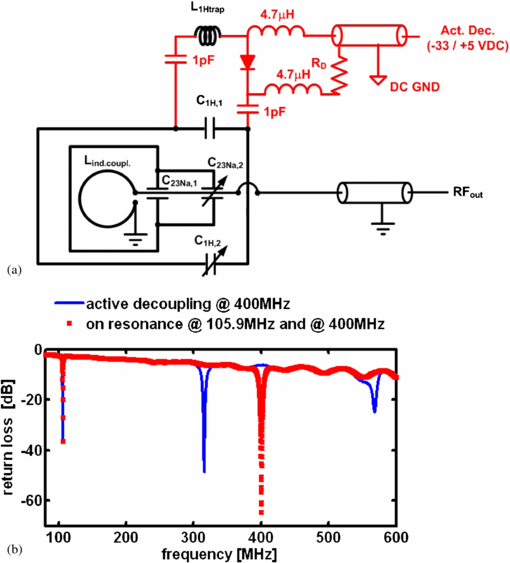

The circuit diagram for the newly developed 1H/23Na surface resonator is presented in figure 1(a). This surface coil was home-built and was composed of a 23Na-tuned surface coil (35 mm length, 25 mm width and 1.5 mm thick silver wire) nested in a larger 1H tuned surface coil (45 mm length, 60 mm width, 1.5 mm thick silver wire). The rectangular loops were wrapped around a cylinder, 42 mm diameter to better fit the anatomy of the rat head in order to increase the depth of the detection sensitivity in the sample. Fixed capacitors were used in the coil's circuit for coarse tuning purposes (C1H,1 and C23Na,1 in figure 1(a): 3.3 and 33 pF, CHB series, TEMEX, France). The resonator was variably tuneable via two trimmer capacitors (C1H,2 and C23Na,2 in figure 1(a): 0.5 to 6 pF, NMQM6GE, Voltronics, USA). Non-magnetic coaxial cable with matching BNC connectors (RG316 and 11BNC50-2-13-133NE, respectively, Huber and Suhner, Switzerland) was used to transmit the RF signal from the receiver coil to the preamplifier of the Bruker MRI system.

Figure 1. (a) Circuit diagram of the newly developed surface resonator with receive-only 1H and transceiver 23Na capability and (b) return loss as a function of frequency as acquired for the same 1H (400 MHz)/23Na (105.9 MHz) resonator with (blue line) and without active decoupling at 400 MHz (red dotted line). The active decoupling caused a peak split at 400 MHz resulting in one peak at 310 MHz and another at 570 MHz.

Standard imageThe design entailed a 1H surface coil presenting a low impedance to the 23Na coil through the use of low value tuning capacitors (3.3 pF, 455 Ω @105.9 MHz) so that the 23Na sensitivity did not decrease through unwanted coupling effects between both coils. At the same time, the 23Na coil coupled with the 1H resonator at the 1H frequency and therefore had to be considered as a part of the entire coil circuit for tuning the structure to 400 MHz. Inductive coupling (20 mm inner diameter loop) was used instead of capacitive matching to couple into the 23Na coil at 105.9 MHz and into the 23Na/1H structure at 400 MHz. A mechanism translating a rotation of a matching rod into a translation of the coupling coil was used to move the inductive coupling coil relative to the surface coil when placed inside the scanner. The 23Na channel could thus be perfectly matched which also achieved excellent matching at the 1H channel at the same time (see return loss in figure 1(b)). Such a design rendered it unnecessary to incorporate a trap circuit into the surface coil which would ultimately degrade the 23Na sensitivity.

To enable the use of the 1H receive-only surface coil in conjunction with the birdcage resonator, the surface coil was actively decoupled during the transmit phase. Although it is possible to geometrically decouple both coils, for example by arranging the orientation of the plane of the surface coil parallel to the B1-field of the birdcage, the accurate geometric decoupling of identically tuned resonators is difficult to set up in practice without the use of a network analyzer alongside the MRI system, and thus it is impractical for in vivo experimentation to rely exclusively on this approach. Consequently, in addition to the use of geometric decoupling by aligning the coils by eye in the MRI system, the active decoupling was incorporated into the design of the 1H surface coil. In this way, an active decoupling signal from the MRI scanner was used to switch the coils resonance on or off at the appropriate time during the imaging pulse sequence. This was achieved by incorporating a PIN-diode switched trap circuit into the resonance structure, designed such that the coil was on resonance as long as the PIN-diode was reverse-biased. The coil had to be switched off-resonance by applying a suitable dc voltage (+5/−35 V), which was supplied by the MRI system. The dc potential was separated from RF ground through the use of high value capacitors (1 nF, CHB, TEMEX, France), while the RF potential was separated from dc ground using RF chokes (4.7 µH, IM4, Vishay, France).

The unloaded-to-loaded quality-factor-ratio (Q0/Ql) was determined via reflection coefficient measurement (s11) using a vector network analyzer (ZVL3, Rhode & Schwarz, Munich, Germany). The return loss measured at the coaxial connector of the coil is shown in figure 1(b). Excellent 1H active decoupling was achieved with the introduced coil design as indicated by a broad peak split at 400 MHz resulting in one peak at 310 MHz and another at 570 MHz. No change in the 23Na frequency was noted during 1H active decoupling indicating strong independence of the 23Na from the 1H surface detector loop.